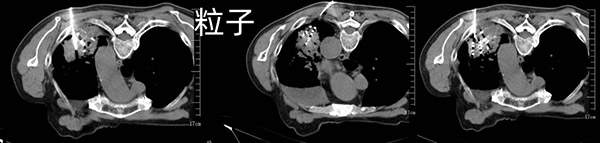

综合患者的状况,首选治疗方案是使用肺癌靶向药物,根据基因检测结果EGFR19外显子缺失突变,丰度1.5%,给予阿法替尼靶向治疗。口服靶向药期间,患者定期复查,一年半后逐渐出现咳嗽、喘息气短,复查肺CT发现左肺上叶病灶增大,同时出现左侧胸膜转移,左肾上腺转移。根据肿瘤进展情况,应更换靶向药物及静脉化疗,不过家属及刘大爷都拒绝进行化疗。根据肿瘤的分期、阶段,再结合患者身体状况,介入科团队拟采用放射性粒子植入术,以控制肿瘤的进展,家属及患者在详细了解方案后对粒子植入的疗法也非常认可。经过充分的术前讨论及准备,手术如期开展,术中按照预先拟定好的TPS计划系统均匀布放43颗粒子,仅30分钟成功实施粒子植入术。术后半个月刘大爷的咳嗽明显减轻,左肺病灶从83X49mm明显缩小到58X21mm。粒子植入术后至今,患者状态一直良好。

放射性粒子植入术后1个月复查左肺病灶从83*49mm缩小到58*21mm,疗效CR